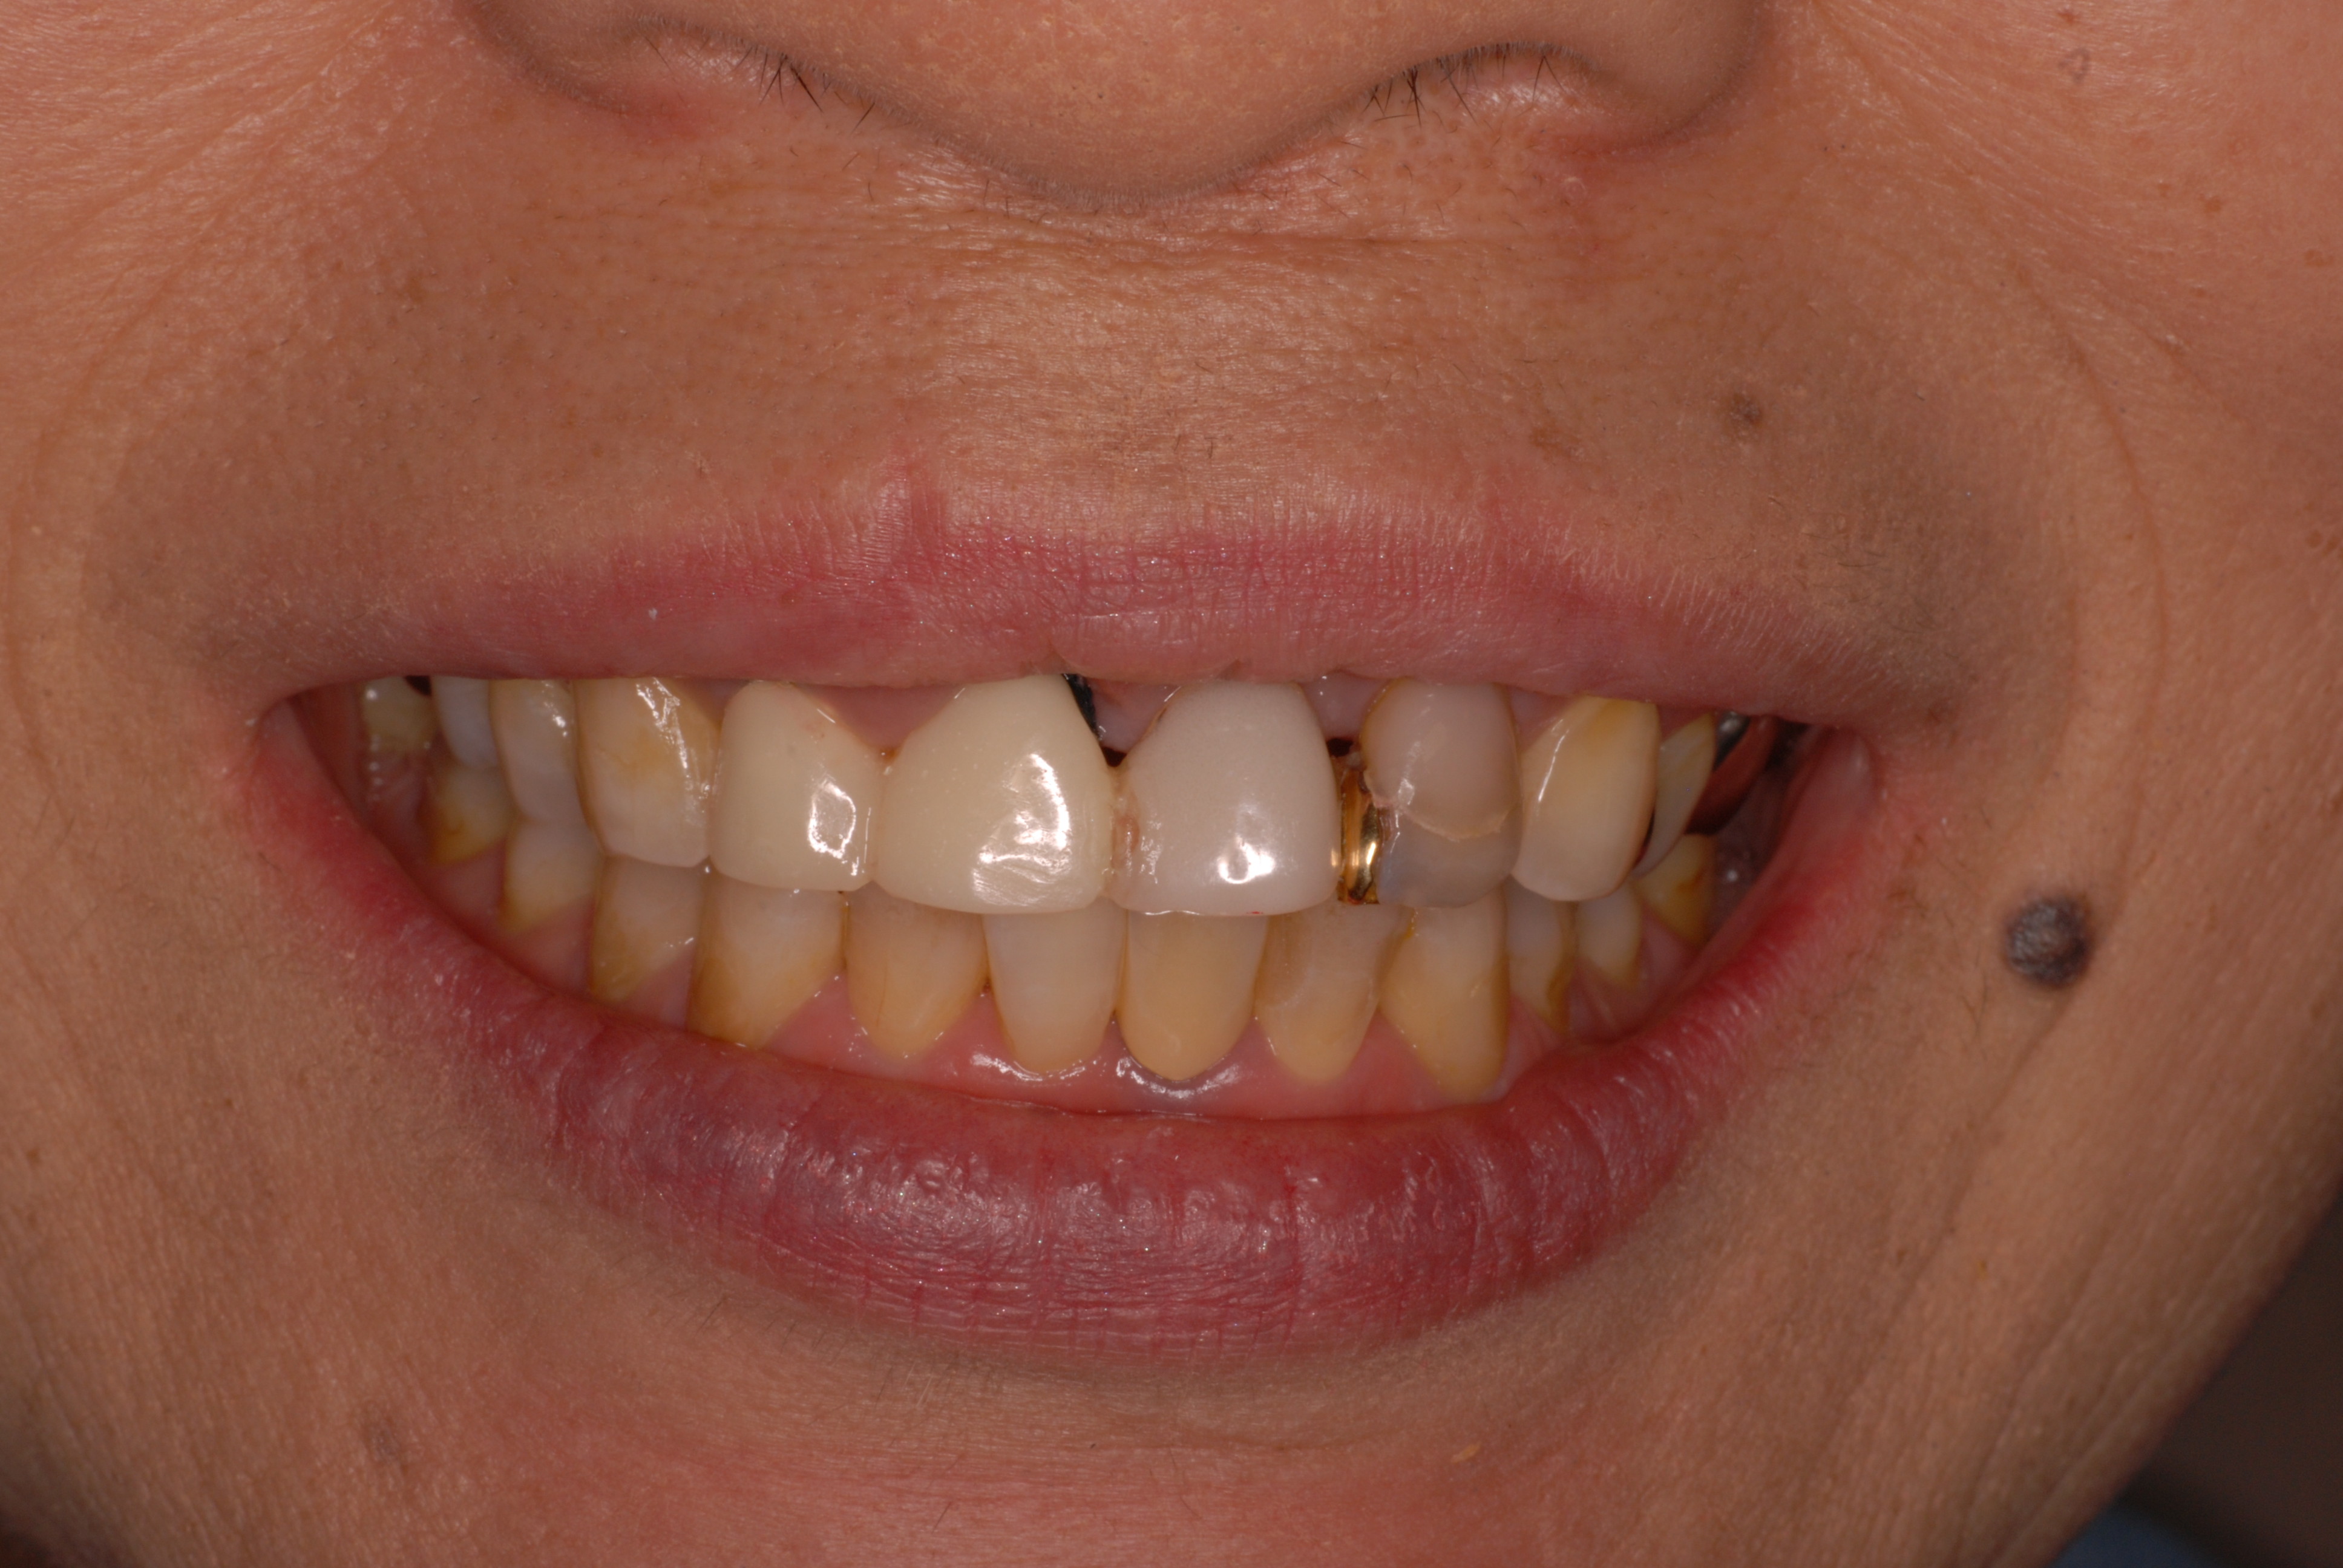

現実を見ればお口の中には“異物”である金歯、銀歯、セラミック、インプラントのオンパレードです。

これ等のものは、異物です。無い方が病気にならず健康でいられるのです。

しかし、保険の場合は質を問わず何か詰めたり被せたりすればお金が払われる仕組みなんです。それも非常に安い値段なんです。しかしそれでも歯周病や神経の処置よりまだましな値段なんですね。